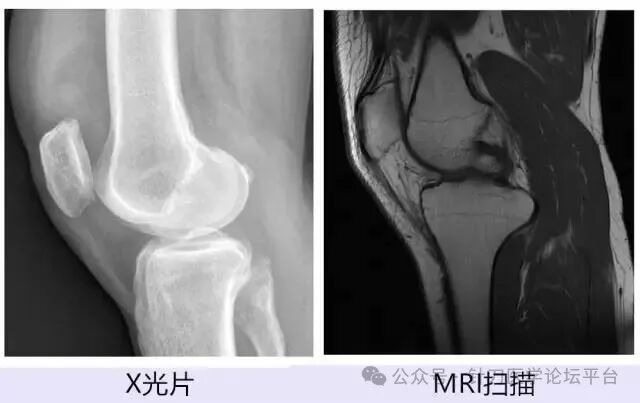

(一)髌韧带上端慢性损伤 过去称为髌骨末端病,表现为髌骨下端疼痛。病变部位为髌骨与髌腱相交部位的损伤或劳损,局部压痛明显,股四头肌抗阻阳性。(二)髌下脂肪垫炎 病变在髌下脂肪组织内,由于损伤或寒湿侵袭等刺激而发生疼痛,也可继发于关节其它组织病变。检查时将髌骨推向下方,另手挤压髌骨下缘产生疼痛。(三)半月板损伤 半月板损伤和髌骨软化症都有交锁现象,但前者为真性的,后者是假性的,结合其它检查不难确诊。(四)骨性关节炎 又称骨关节病,多见于老年病人,临床表现为:关节伸屈到一定程度时引起疼痛,伸屈受限,下蹲困难等。X线片表现为骨质疏松,关节间隙变窄,软骨下骨质硬化,关节边缘增生等。而髌骨软化多见于中、青年人,关节疼痛在髌股关节面和髌骨周围,半蹲位疼痛加剧。